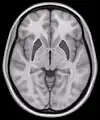

Horizontal slice of MRI-image showing the putamen. The other nuclei of the basal ganglia (caudate nucleus and globus pallidus) can be seen as well.- Putamen